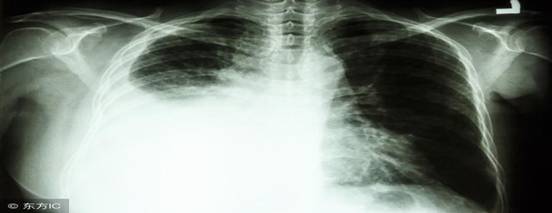

得了肺癌后 身体会出现哪些细微征兆 肺癌是发病率和死亡率增长最快,对人群健康和生命威胁最大的恶性肿瘤之一。由于肺癌发展迅速、恶性程度高,一旦出现胸闷、血痰、呛咳、胸痛等临床症状,大多已经是中晚期,治疗效果不佳。所以早发现、早治疗就显得尤为重要。虽然肺癌的早期症状不明显,而且容易与感冒、支气管炎、肺炎等病相混淆。但我们还是要了解一些细微的征兆,一旦发现,及时去医院检查。 局限性喘鸣音:单侧性局限性喘鸣声,特别在吸气阶段的喘鸣音,咳嗽后并不消失,是肺癌早期体征之一,但为时短暂,容易被忽视。 声音嘶哑,吞食困难:转移压迫喉返神经,可致声音嘶哑,却无咽痛及上呼吸道感染的其他症状。压迫食管引起吞咽困难,甚至发生支气管一食管瘘,导致肺部感染,压迫气道严重时可窒息而死。 骨关节肿痛:肺癌早期患者骨关节常会发生不明原因的肿痛,尤其以下肢较为明显,时常还会伴有费凹陷性水肿,发热。